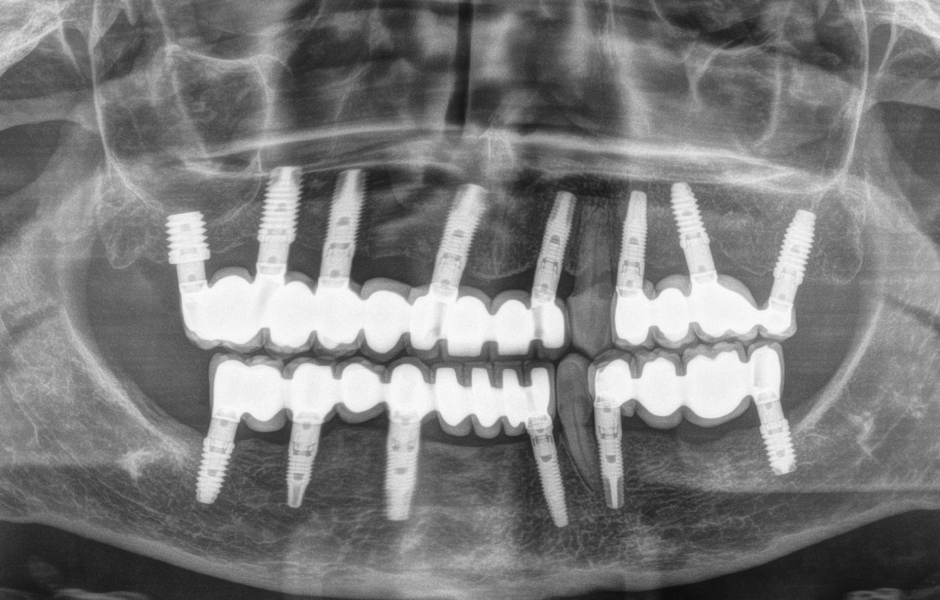

Případ popisuje sanaci 65leté pacientky s pokročilým onemocněním parodontu. Pacientka řadu let nosila horní a dolní částečné snímatelné náhrady. Špatný stav zbytkového chrupu začal zhoršovat retenci náhrad a byl příčinou bolesti kotevních zubů. U většiny zbývajících zubů byla zjištěna pohyblivost II. a III. stupně – u zubů 23 a 33 pak stupeň viklavosti I.